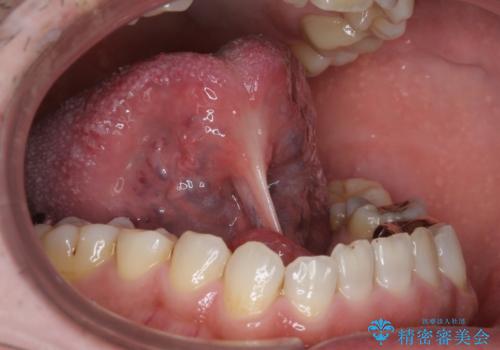

- 滑舌の悪さに長年悩まされており、意を決して手術での治療を希望し来院。

術前に舌の動きを確認した後、局所麻酔下での施術となりました。

局所麻酔下にて施術しました。